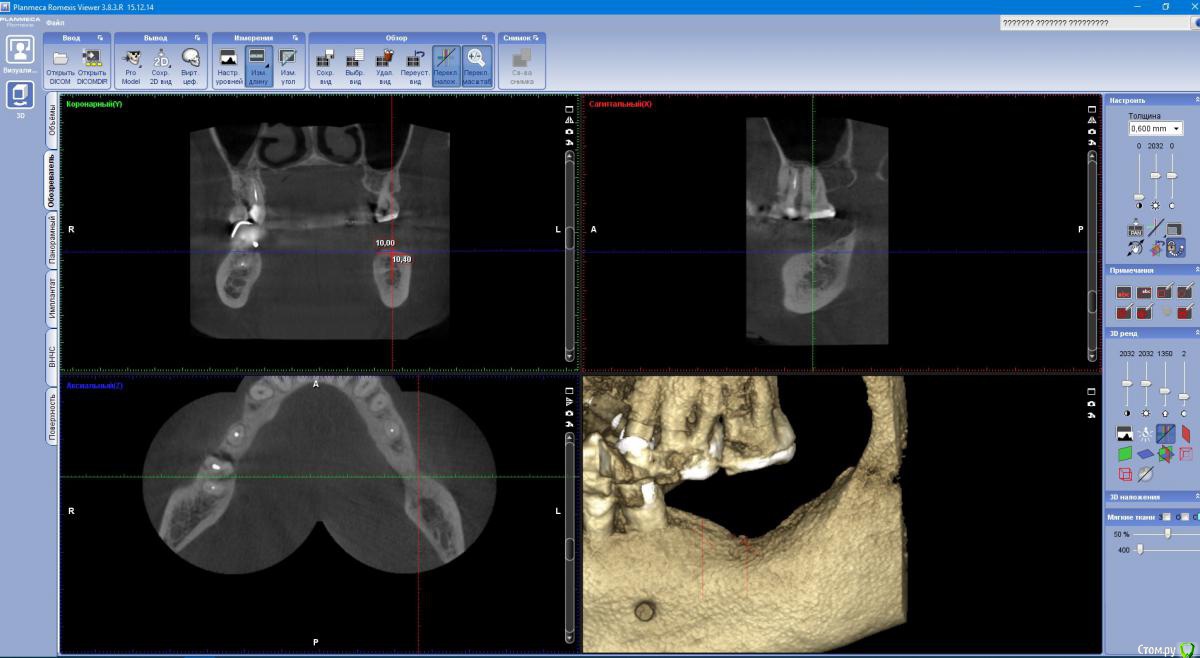

indie Опубликовано 4 октября, 2018 Поделиться Опубликовано 4 октября, 2018 Здравствуйте, колеги. Решил заняться имплантацией, думал выбирать только идеальные случаи, по Гудману так сказать. Но таких оказалось не больше 1-2 месяц, потому взялся за не совсем идеальные. По этой причине нужна помощь опытных врачей в планировании и прогнозировании возможных осложнений. Пац. 52 года. КТ прилагаю . Планируются имплантанты в позицию 36 37 MIS C1. 36 - 4.2x10mm, 37-5x8mm. Что смущает, во первых вертикальный дефицит твердых и мягких тканей, особенно в зоне 37, во вторых стоит ли вообще ставить имплантат в позицию 37. Если ставить, то можно ли обойтись без аугментаций? Ну и вообщем интересно, какой стратегии держатся в подобных не идеальных ситуациях? Спасибо. Ссылка на комментарий

Nazim_NV86 Опубликовано 4 октября, 2018 Поделиться Опубликовано 4 октября, 2018 (изменено) Скачайте свежую версию Planmeca с официального сайта. Уже 5.0 вышла давно. Это абсолютно бесплатный софт с функцией сохранения. Изменено 4 октября, 2018 пользователем Nazim_NV86 Ссылка на комментарий